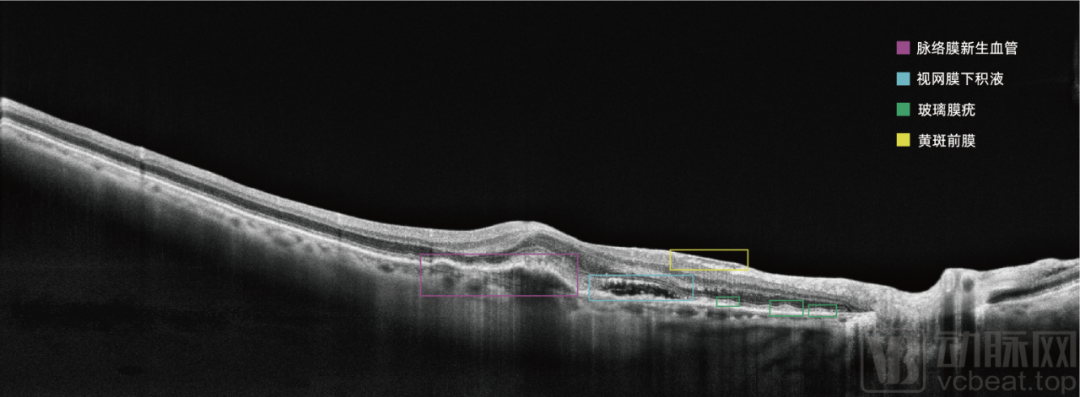

OCT是眼底病临床诊疗的权威检查设备,但传统OCT操作步骤复杂,阅片依赖高水平专业医生,限制了OCT在基层的普及应用。利用先进的眼科AI技术赋能,正是解决我国基层眼科医疗资源不足的有效途径。

比格威全自动人工智能OCT实现了瞳孔自动定位对焦,减少了因手动操作不熟练导致的拍摄不成功;通过与检查环节紧密衔接的语音提示,减轻了操作人员进行引导的工作负担,也让患者体验更加友好;设备集成比格威行业领先的眼科AI算法,对疾病病灶区域进行准确识别和自动标注,能够为基层眼科医生提供有价值的诊疗信息。比格威医疗开发完成的全自动人工智能OCT BV1000,让基层眼科真正拥有了一台会用、好用的OCT。

作为一家深耕眼科AI的创新企业,比格威在一开始就走上了一条差异化的道路,目前市场上大多数眼科AI产品为基于眼底彩照进行糖网辅助诊断,比格威医疗在进行糖网AI开发的同时,率先进行眼科 OCT影像的AI研究并形成了成熟产品。

眼底彩照影像为视网膜二维图像,而OCT获取的是视网膜三维结构信息;OCT影像包含的视网膜结构层次信息丰富复杂,AI算法开发的难度较眼底彩照更大。比格威医疗基于OCT影像对年龄相关性黄斑变性(AMD)等十余种眼底疾病的分类、识别、病灶分割算法进行持续研究,取得一系列创新成果,在这一技术领域申请专利70余项,已获授权的发明专利达30余项。

比格威医疗眼科影像AI研究,从影像类型来说,不仅开展了OCT和眼底彩照影像的AI研究,还进行了眼底荧光照影、角膜共聚焦显微成像、裂隙灯、角膜地形图等影像的AI研究;从疾病种类来说,包括了年龄相关性黄斑变性(AMD)、糖网、青光眼、高度近视、中心性浆液性脉络膜视网膜病变、早产儿视网病变(ROP)、角膜神经病变、圆锥角膜、角膜溃疡、眼外伤等疾病的AI研究。